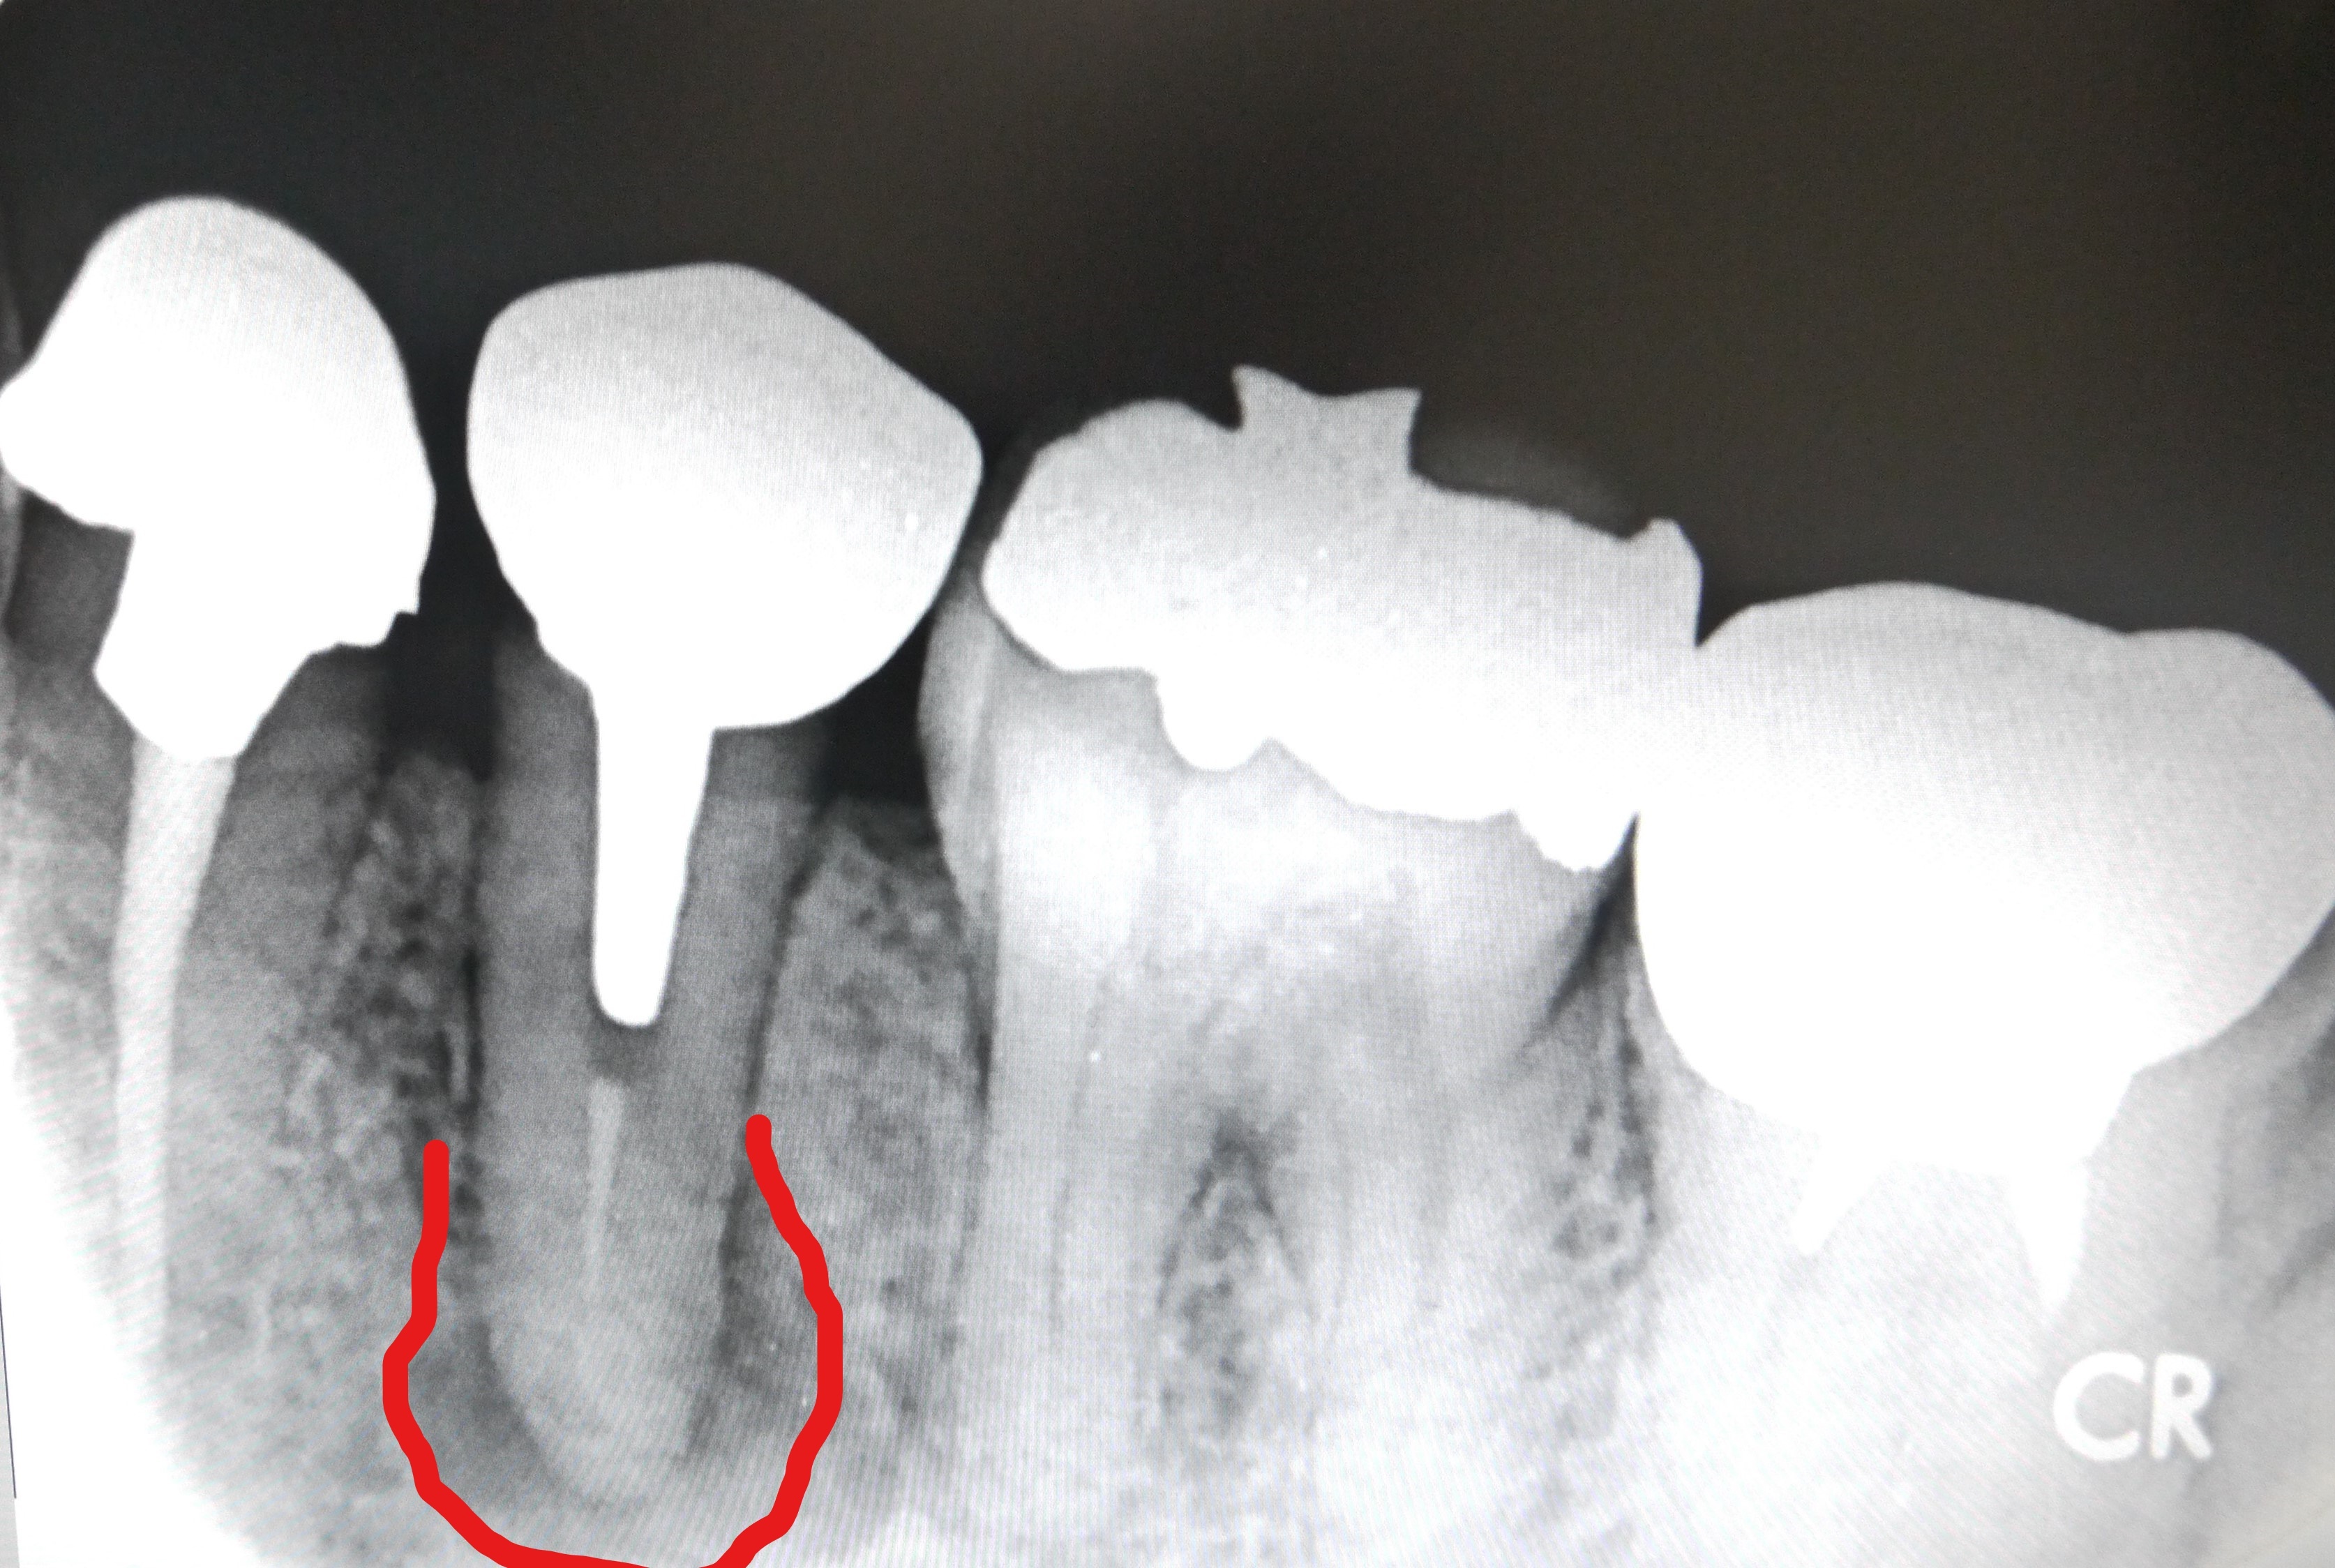

根管の中に薬(ガッタパーチャとシーラー)をつめていきます。(根管処置)

この際、根の長さぴったりまで加圧しながら薬を詰めていくことが

腫れの再発を防ぐために最も重要です。